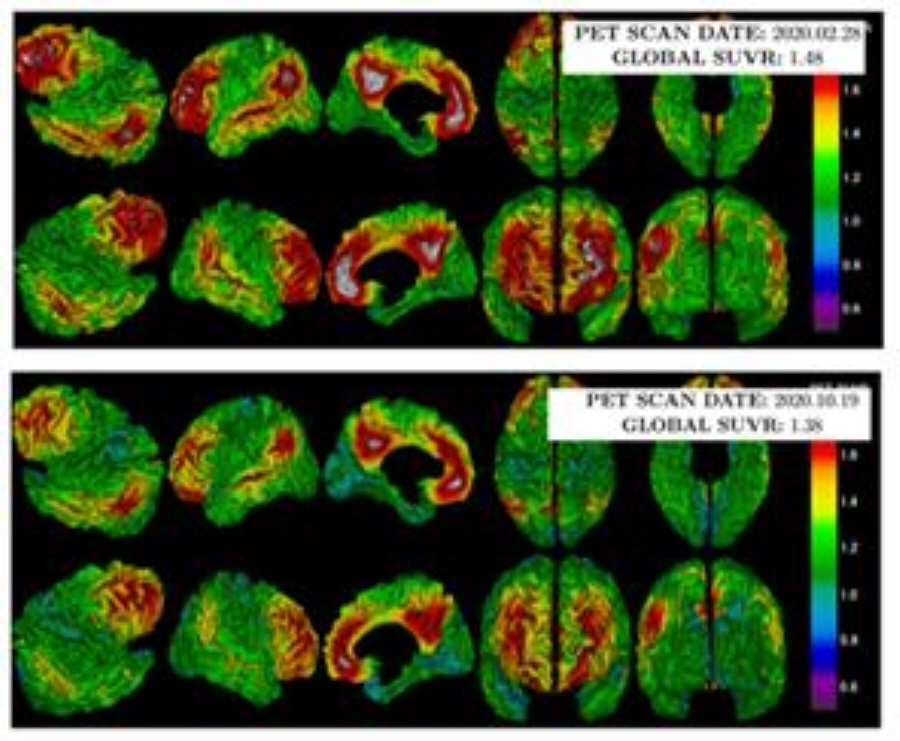

환자들은 개방술을 받은 6개월 동안 약을 복용했고 연구 중에 아밀로이드 침착을 확인하는 PET 검사를 시술 전후로 2번 진행했습니다.

연구팀은 PET 검사 수치를 보정해 ‘표준화 섭취계수율’로 아밀로이드 감소 정도를 파악했다. 보호자를 대상으로는 행동과 심리를 기반으로 치매 중증 정도를 파악하는 CGA-NPI(Caregiver-Administered Neuropsychiatric Inventory)을 실시했다.

연구 결과, 마지막 검사의 표준화 섭취계수율은 환자 평균 0.986으로 첫 검사 결과인 1.002보다 0.016 하락해 아밀로이드가 감소한 것으로 밝혀졌다. CGA-NPI 점수는 8점에서 2점으로 떨어지며 보호자가 느끼는 환자 문제 행동도 호전됐다.